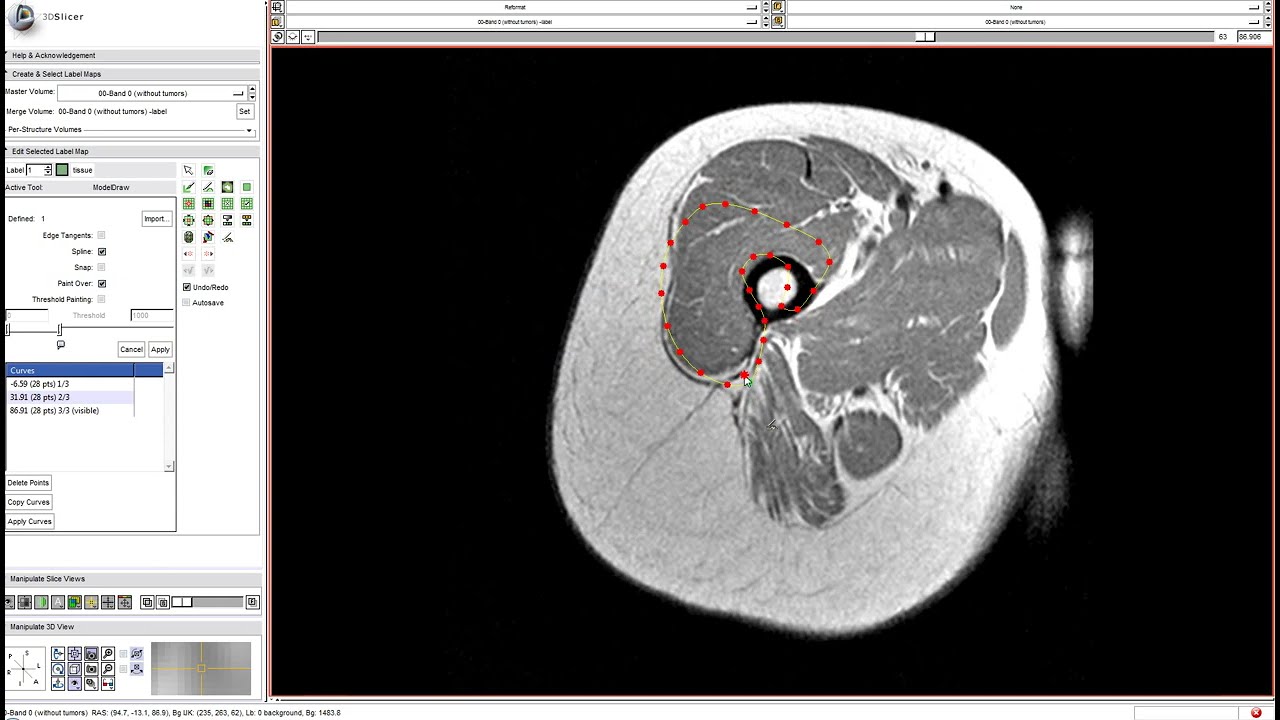

Isn’t maybe something the OP meant what we had at the very end of the Slicer 3 days, the tool with the control points? I think it was called ModelDraw :slight_smile:

I might not exactly get the idea based on the description, but if yes, well… :slight_smile: I know, I know… but I did like that tool, and the functionality!

Here is video on how it worked:

Attila